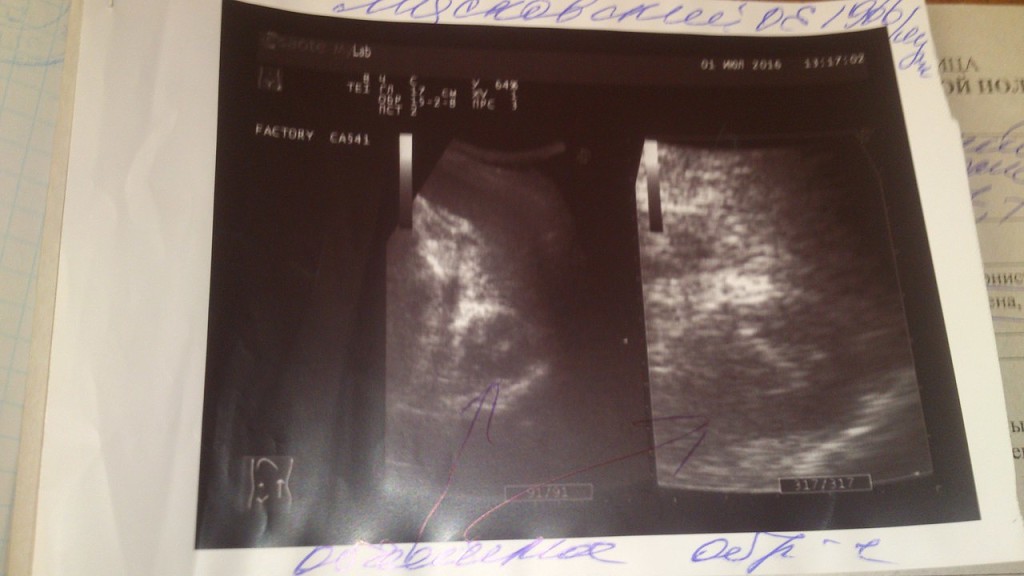

Наш папа, Мясковский Олег Евгениевич, 1966 года рождения, за последние три года пережил инфаркт и инсульт.  Сейчас стало известно, что причиной всему стала опухоль надпочечника — ФЕОХРОМОЦИТОМА. Из за активности опухоли восстановление невозможно. Она же провоцирует ухудшения. Срочно нужна дорогостоящая операция по удалению опухоли. Нужной суммой наша семья не располагает. Мы просим помощи у всех. Помогите нам спасти папу.